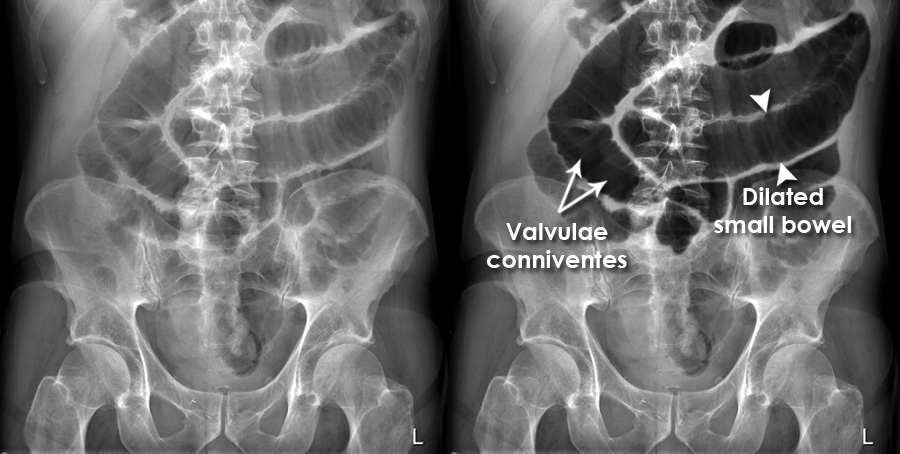

某阿伯肺炎入院,但住院期間抱怨便秘3-4天,KUB看起來腸氣多,大、小腸腫脹,懷疑ileus,可以給什麼藥物處理?

常見於術後腸子蠕動功能尚未恢復、腹膜炎、retroperitoneal syndrome、脊髓受損、代謝性問題(uremiaDM昏迷、黏液性水腫、低血鉀)。因為腸子不會動(無腸音),通常不會痛,主要以腹脹、便祕表現(KUB可見到很多腸氣,而且不固定位置,會移動)